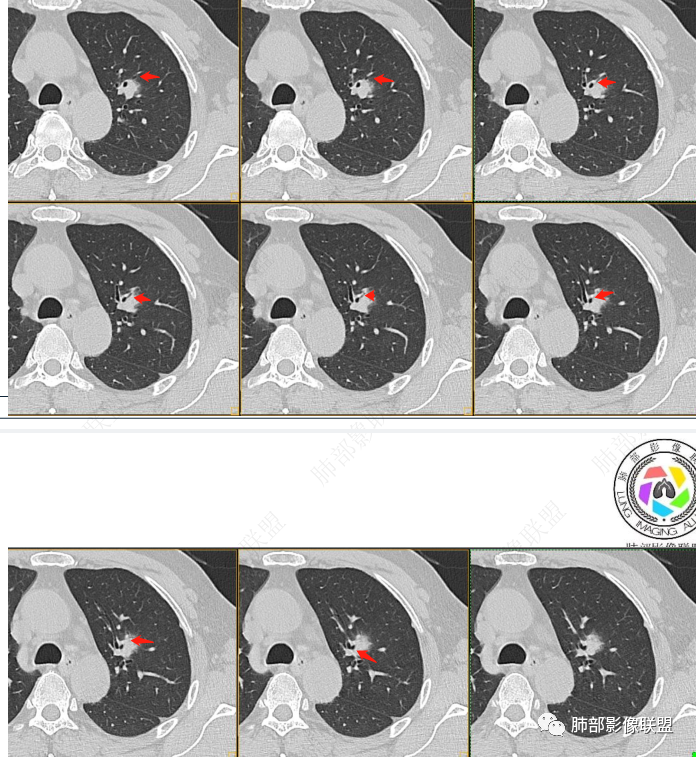

我标示一下,说一下个人的想法

初始病灶应该是这里

病灶朝前、外侧进展

病灶包括两部分

1、实性2、周围GGO

目前看支气管通畅

实性部分强化明显,边缘平直

2、病灶以实性密度为主,前、外侧蔓延,GGO部分边界清楚,部分欠清

支气管未见受明显侵犯,未见阻塞,壁增厚,狭窄或扩张。

软组织+重建;病灶实性部分不是类圆形,密度相对均匀柔和。

肺门区病灶与支气管关系不密切,强化显著、磨玻璃晕等等容易想到的是肺腺癌。而不首先考虑与支气管密切相关恶性肿瘤,如鳞癌、类癌、粘液表皮样癌等等。

1、连续3年观察,病灶逐步增大,符合惰性恶性肿瘤。2、支气管壁增厚,腔内内壁无变化——病灶长轴沿支气管周围蔓延;朝外走,内侧没有,提示病灶间质为主,与支气管无关。

3、GGO长期存在,朝外蔓延,支持恶性特点。

支持淋巴瘤的关键点:1、间质为主;2、与支气管无关;3、边缘GGO的长期存在支持恶性

因为与支气管无关不支持腺癌,还是要警惕淋巴瘤。